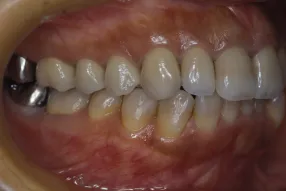

初診時

治療完了時

| 患者様のお悩み | 外傷で歯が抜けた |

| 治療法・使用素材 | インプラント治療の後、セラミック治療 |

| 患者様の年代 | 20代 |

| 治療開始年齢 | 20代 |

| 治療にかかった期間 | 8か月 |

| 性別 | 女性 |

| この治療のリスクについて | インプラントが正しい位置に入るかどうか |

| 治療にかかった費用 | 45万円 |